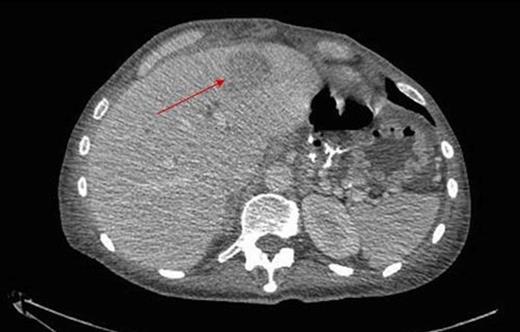

During inpatient stay, she became haemodynamically unstable with spiking temperatures and an elevating white cell count. She also complained of bilateral discolouration of her toes and examination revealed increasing oedema with diminished pedal pulses. A contrast CT scan of the abdomen confirmed ongoing collections with evidence of an aortic thrombus extending into the left iliac artery, presumed to be the embolic source for her vascular findings (figure 2 & 3). She underwent a further laparotomy and washout, and was heparinised postoperatively. There was resolution of vascular symptoms and evidence of improvement in peripheral perfusion postoperatively, and the patient was eventually discharged.

Thrombus within the distal aorta shown by a filling defect (red arrow)